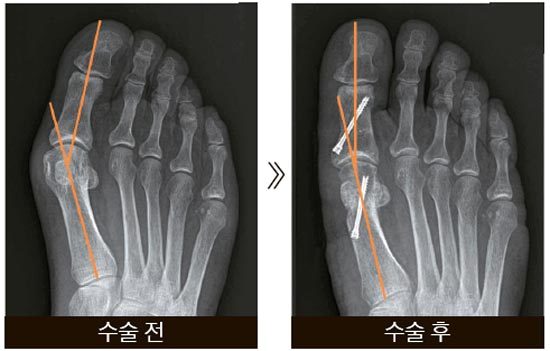

또한, 복합 골절이나 압박 골절과 같이 더 복잡한 경우에는 수술이 필요할 수 있으며, 뼈가 조각나거나 비스듬하게 부러진 경우에는 금속판을 추가적으로 사용할 수 있습니다.

발가락 골절은 다양한 형태로 발생할 수 있으며, 이에 따라 치료 방법이 달라집니다. 골절의 종류에 따라서는 수술이 필요한 경우도 있습니다. 주요 발가락 골절 유형은 다음과 같습니다:

- 뼈가 사선으로 부러진 경우: 이 경우 깁스만으로는 충분한 고정이 되지 않으므로 수술이 필요할 수 있습니다.

- 수술 치료: 뼈가 심각하게 파열되거나 개방성골절인 경우 수술이 필요합니다. 이 경우 수술비용은 약 60만원에서 150만 원까지 다를 수 있으며, 이 비용에는 입원비, 식비, 약값 등이 포함될 수 있습니다.